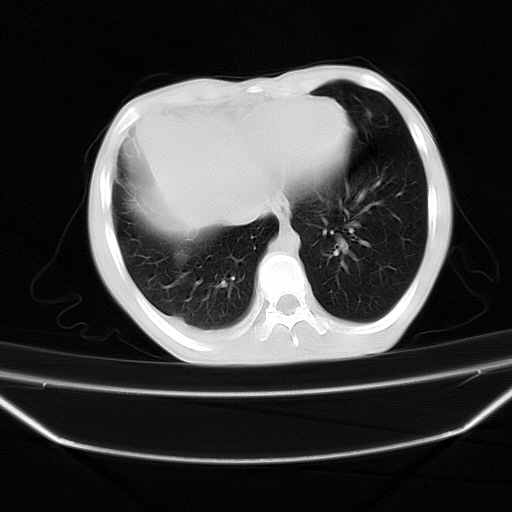

以下是引用zjzjr在2008-7-20 12:57:00的发言:[br]考虑为生殖源性肿瘤(内胚窦瘤),侵袭性胸腺瘤可能性大;右侧少量胸腔积液。

以下是引用xinliheng001在2008-7-20 21:17:00的发言:[br]右纵隔巨大分叶状软组织均质密度肿块,右上肺叶受压明显,纵隔右移、胸膜受累有少量积液和结节样增厚。应增强扫描一定会有更具诊断价值的信息。

以下是引用xinliheng001在2008-7-20 21:17:00的发言:[br]右纵隔巨大分叶状软组织均质密度肿块,右上肺叶受压明显,纵隔右移、胸膜受累有少量积液和结节样增厚。应增强扫描一定会有更具诊断价值的信息。